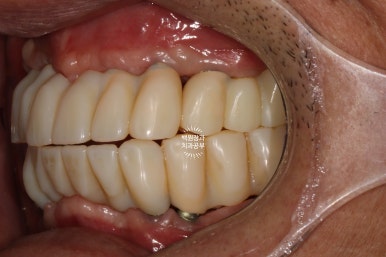

그리하여 완성된 최종보철물입니다!!

옛날부터 임플란트 틀니용으로 사용하시던 임플란트 3개는 임플란트 주위염이 조금 있어 약~간 쇠기둥 색깔이 보인다는 단점이 있긴 하지만, 다른 임플란트들은 꽤나 예쁘게 제작이 되었네요.

위 아래 교합면 사진을 보시면, 과연 이게 임플란트인가? 싶으실거에요. 치아에 지르코니아 크라운을 붙인 것과 큰 차이를 못느낄 정도로 정말 자기 치아같이 예쁘게 제작된 임플란트 크라운을 보실 수 있습니다!!